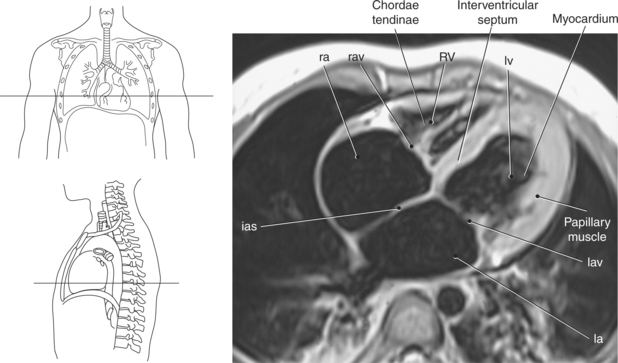

The walls of the heart consist of three layers: (1) epicardium, the thin outer layer that is in contact with the pericardium; (2) myocardium, the thick middle layer consisting of strong cardiac muscle; and (3) endocardium, the thin, endothelial layer lining the inner surface. The endothelial layer also lines the valves of the heart and is continuous with the inner lining of the blood vessels. The heart is divided into four chambers: the right and left atria and the right and left ventricles. The two superior collecting chambers called atria are divided by the interatrial septum. During embryonic development an oval opening exists within the interatrial septum called the foramen ovale. This opening allows blood flow between the right and left atria during fetal lung development. At birth, the foramen ovale closes, leaving a small depression in the septal wall called the fossa ovalis in the adult heart. The two inferior pumping chambers called ventricles are divided by the interventricular septum (Figure 6.39).

The right atrium forms the right border of the heart and receives deoxygenated blood from the body via the superior and inferior venae cavae and from the coronary sinus and cardiac veins that drain the myocardium. A small muscular embryonic appendage, the right auricle, projects upward and toward the left from the right atrium, covering the root of the aorta (Figure 6.40). The right ventricle lies on the diaphragm and comprises the largest portion of the anterior surface of the heart. It receives deoxygenated blood from the right atrium and forces it into the pulmonary trunk for conveyance to the lungs. Projecting off the inferior surface of the ventricular walls are conical-shaped projections of cardiac muscle called papillary muscles that anchor the cusps of the tricuspid valve to the right ventricle (Figure 6.39). The left atrium lies posterior to the right atrium and is the most posterior surface of the heart. It also has an embryonic appendage, the left auricle, that projects to the left of the pulmonary trunk over the superior surface of the heart. The left atrium receives oxygenated blood directly from the lungs via the four pulmonary veins (two on each side). The left ventricle forms the apex, left border, and most of the inferior surface of the heart. It receives oxygenated blood from the left atrium and pumps it into the aorta for distribution throughout the systemic circuit. The myocardium of the left ventricle is normally three times thicker than that of the right ventricle, reflecting the force necessary to pump blood to the distant sites of the systemic circulation (Figures 6.41 through 6.52). Two papillary muscles project from the ventricular walls to anchor the bicuspid valve to the ventricle (Figures 6.39 and 6.47).

The two atrioventricular valves are found at the entrances to both ventricles and function to prevent backflow of blood between the atria and ventricles during ventricular contraction. These valves have leaflets that are attached to the papillary muscles by thin cords of fibrous tissue called chordae tendineae. The right atrioventricular valve, with three leaflets, is called the tricuspid valve, and the left atrioventricular valve, with two leaflets, is called the bicuspid (mitral) valve (Figures 6.39, 6.43, 6.44, 6.47, and 6.48).